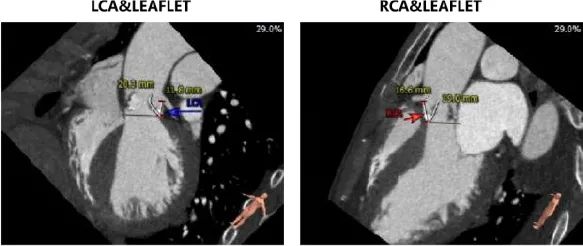

主动脉根部评估:

左冠开口高度12.0mm,右冠开口高度17.8mm,左冠高度较低,根据瓦氏窦内径和瓣叶长度综合判断,左冠存在较高堵塞风险;左室腔增大,心室壁未见明显增厚。